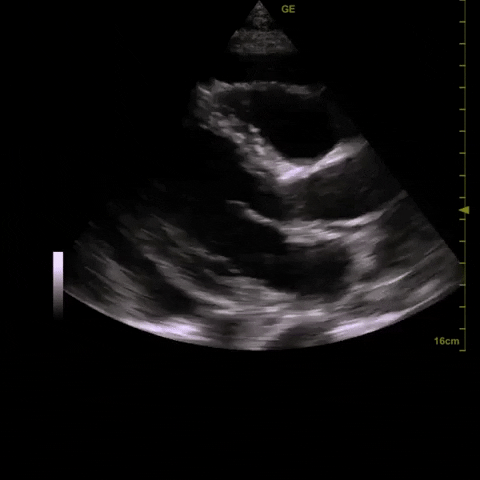

2) ?pericardial effusion (small one noted on initial CT scan)

A diagnostic echocardiogram was performed which was consistent with the POCUS findings. In discussion with Cardiology, a percardiocentesis was performed and over 1L of fluid was aspirated from the pericardial sac (good access from the A4C window). The patient tolerated this well and had a very modest increase in blood pressure following the procedure.

- There are several echocardiographic signs of increased intrapericardial pressure: RA collapse, RV diastolic collapse, and increased mitral/tricuspid inflow variation